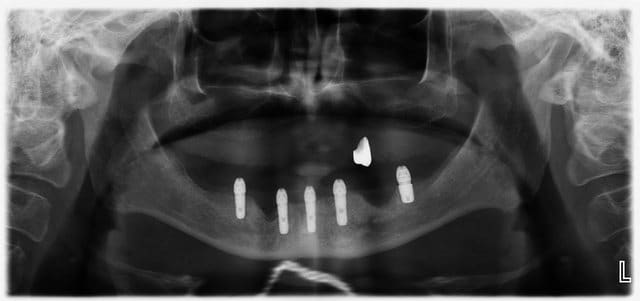

Mon premier complet immédiat sur implants fait cette semaine...

Implants posés mercredi matin, bridge posé jeudi matin...

Dsc 0037 clomyw - Eugenol

Dsc 0038 cff4sp - Eugenol

Dsc 0039 n8y16y - Eugenol

Dsc 0040 vdb4vc - Eugenol

Ori h2jjrj - Eugenol

S8ysxdzhdqgw00w4q6m07a5d47q2 - Eugenol

Blague à part, son appareil à 15 ans, il veut la même chose en haut qu'en bas... pas d'os... je suis en train de me creuser la tête pour trouver une solution convenable.